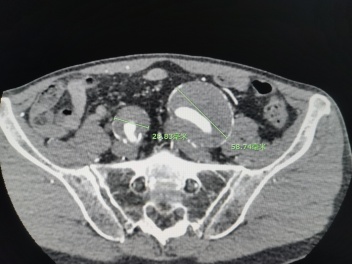

近日,60岁的张老伯因突发剧烈腰痛前往复旦大学附属金山医院就诊。检查结果显示,除输尿管结石外,他体内还潜藏着多处致命隐患——双侧髂动脉瘤(左侧直径达58mm,右侧29mm),且右侧髂外动脉已完全闭塞,导致日常行走举步维艰。